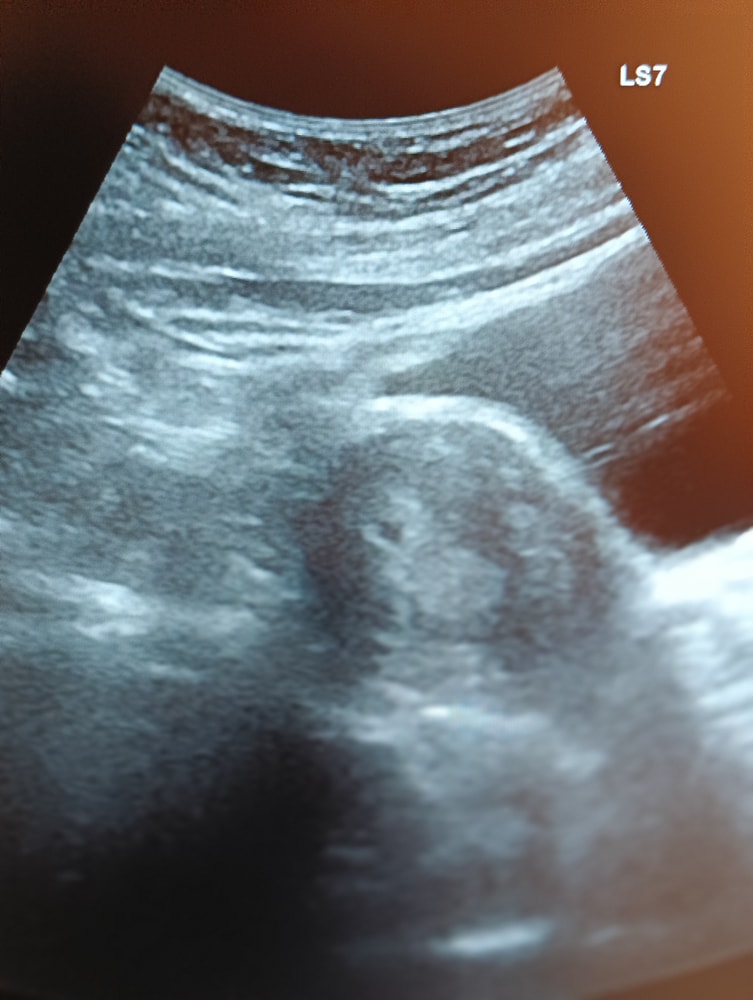

В матке. Всё как и должно быть. Срок поставила 3-4 недели и 9мм. В интернете много статей читала, что в 3-4 недели размер гораздо меньше, а в 7-8 он только достигает таких размеров.

На УЗИ было только темное пятнышко, но размер большой, ведь при таком размере уже виден эмбрион, а тут ничего не видно

Так 9 мм это плодное яйцо и ранний срок 5-6 недель акушерских или 3-4 от зачатия,в 7-8 недель там эмбрион 10-15 мм,а не плодное яйцо,это разные параметры

В 7 недель уже эмбрион 9 мм, а не плодное яйцо. Всё у вас в порядке. ПЯ может быть любых размеров, главное, расти в динамике минимум на 1 мм в день.

Вы путаете эмбрион и плодное яйцо, все у нас нормально эмбрион на данном сроке ещё не может быть. У меня в 5.2д плодное было 10мм, а в 6.5д эмбрион был 8мм